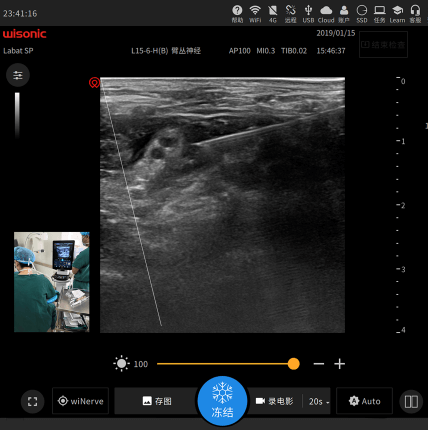

wiShow – Teaching Recording

Support USB Live Camera.

Simultaneously Record Scanning Gesture,

Ultrasound Images and Voice .

On-site Projector Teaching for

Long Time Recording.